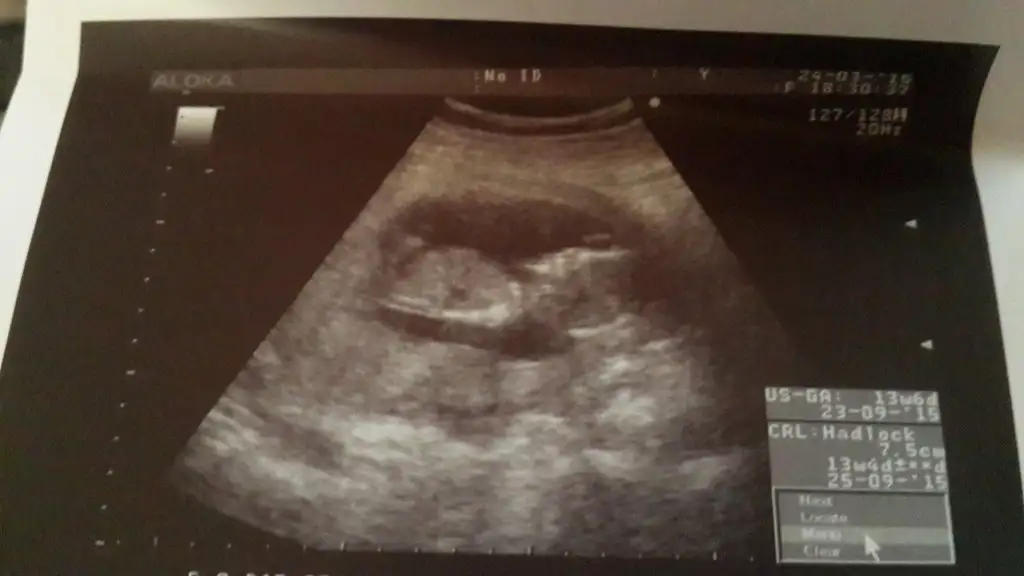

Dikkatlice baktım uzun uzun canım kordonu yukarı eğilimli olsada cikinti yok kız bebis gibi duruyor ama ben senin bebis erkek olduğunu hissediyorum nedense baska doktora gittiniz hic erken hafta yanilma oluyor hem zaten kesin kız da dememiski ben senin yerinde olsam başkasında gorunurdum hayirlisi olsun inşallahArkadaşlar dünkü ultrasonumda bu çıkıntı ne sizce ?kordon mu ki

Doktorum kıza benziyor dedi?tecrübeli arkadaşlarım bi bakarmisiniz? Eki Görüntüle 1470772

Nub cizgisi parelel se hele sizin bebisde olduğu gibi kordonu parelel se kız yukarı egilimli oluncada erkek bebis oluyor sizinki kız bence ogrenince yazarsınız tahmin tutup tutmadığını öğrenmiş oluruz

Bende burdan ve internetten baya bi arastirdim kiz diyorum ben bu bebise ama burdaki arkaEki Görüntüle 1471771 canım bakabilirmisin

Bende burdan ve internetten baya bi arastirdim kiz diyorum ben bu bebise ama burdaki arkadsslsr daha iyi tahminde bulunurlar eminim :))Eki Görüntüle 1471771 canım bakabilirmisin